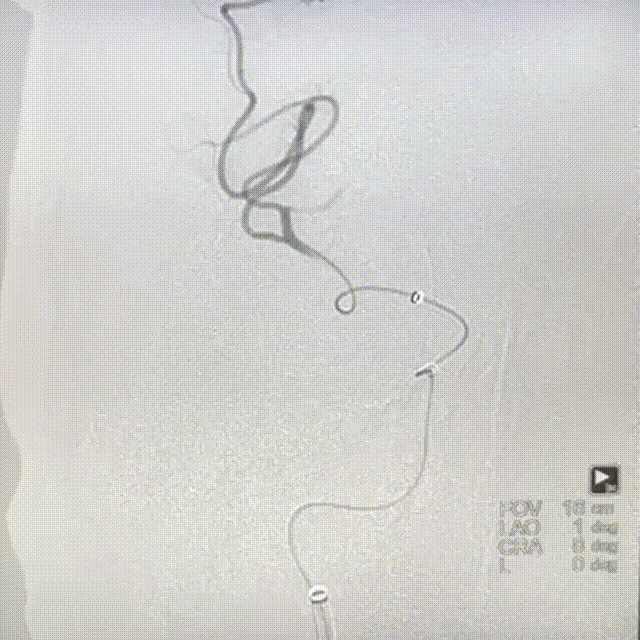

支架输送及定位:

经QUEEN-track微导管将4.0mm*25mm Neurohawk取栓支架输送至病变部位,直至支架远端显影超过血栓,定位时确保血栓位于支架有效长度的中后段。

4

支架释放:

固定支架推送杆,缓慢回撤微导管,释放Neurohawk取栓支架,微导管的头端必须撤至显影段远端露出。支架后程释放时,支架推送杆给张力的同时回撤微导管。Neurohawk取栓支架全身通体显影,可以通过3根显影丝,观察支架打开情况,支撑性较好。

WAVE-track颅内血栓抽吸导管上行至大脑中动脉M1段后,负压抽吸,抽拉结合,取出血栓。WAVE-track颅内血栓抽吸导管0.070inch大口径内腔,血栓抽吸能力强;管体近端PTPE,远端超柔软材料兼顾支撑性和到位性,易推送抗扭折。